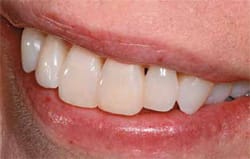

| Final result after bonding with BeautiBond and Beautifil II(View Figure) | In-treatment view of the direct resin restorations performed with BeautiBond and Beautifil II.(View Figure) | ||||||

| Final smile view of the restored anterior dentition.(View Figure) | |||||||